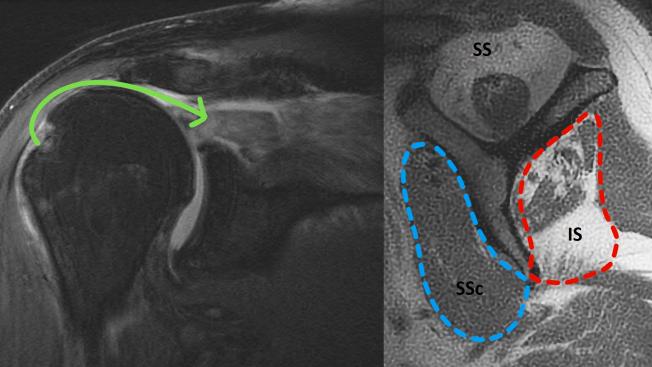

尽管已经开发出各种治疗方法,但不可修复的肩袖撕裂(IRCT)的手术治疗仍存在争议。最近,可生物降解的肩峰下球囊间隔器(InSpace,史赛克公司;密歇根州卡拉马祖)的植入在治疗某些IRCT方面引起了相当大的关注。据报道,球囊植入的结果并不一致,这可能是由于适应症和技术方法不同所致。本文的目的是介绍一种可重复的关节镜下肩峰下球囊植入技术,并回顾迄今为止发表的关于该手术疗效和结果的文献。